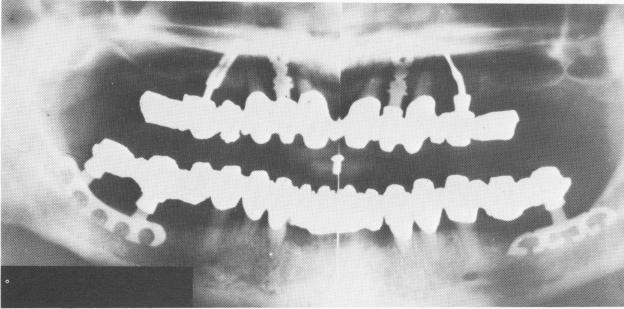

Fig. 11-208. Another series of blade designs. In this maxilla there is a mesiodistal blade in the right tuberosity, an obliquely placed buccopalatal blade in the right bicuspid area avoiding the sinus, a single tooth blade in the left central incisor region, and a transverse oblique, mesially directed blade in the left second bicuspid area avoiding the anterior extent of the antrum. The mandible contains a mesiodistal blade.

2 Series of blade implant designs in maxilla and mandible